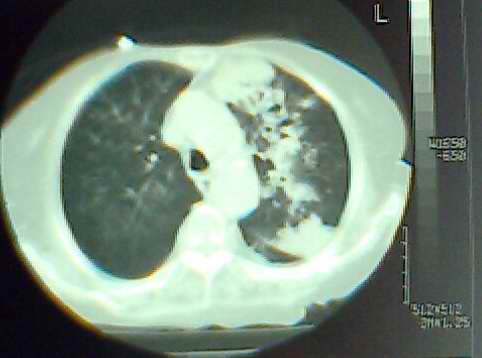

以上是2009-05-25的照片。

以下是引用hhx58在2009-9-11 19:48:00的发言:[br]有4个是心电监护的电极。[br]ct图片可见有肺气囊。但未拿到片上传。

以下是引用37度在2009-9-12 11:54:00的发言:[br][br] [br] 支气管扩张合并混合型感染 [br] [br]

以下是引用dyqct在2009-9-12 8:42:00的发言:[br]慢性支气管炎合并间质纤维化、肺气肿、支气管扩张、感染。建议ct进一步检查。

以下是引用黑白光影在2009-9-12 16:43:00的发言:[br]慢支并感染(霉菌?)